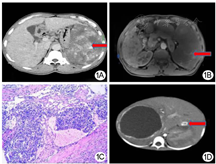

病例1,患者男性,53岁。因"腹胀8 d"入院。腹部查体可触及肿大脾脏,无压痛、叩痛。实验室检查无异常。腹部CT动脉期肝脏可见小结节样强化,脾内呈现结节状血管样强化,门静脉期强化明显(图1A);MRI动脉期脾脏可见"地图样"不均质强化(图1B)。术前诊断为肝胆管错构瘤合并脾血管瘤。行开腹肝组织穿刺活检、巨脾切除术,术中可见巨大的脾脏(23.0 cm×14.0 cm×5.5 cm),肝、脾表面可见多个灰白、灰褐色结节。手术时间3 h,未输血。术后第8天患者出院。病理诊断为肝血管内皮瘤,脾卡波西样血管内皮瘤(kaposiform hemangioendothelioma,KHE),切缘净(图1C)。免疫组化:CD31、CD34、平滑肌肌动蛋白、波形蛋白均阳性,增殖抗原Ki-67指数8%。于出院后15个月随访,患者正常生存,近期体检未复发。

病例2,患儿女性,1岁。因"发现腹部膨隆及间断发热、咳嗽1月余,加重伴气促20 d"入院。查体见腹膨隆,右侧肋缘下可触及肿大肝脏,伴叩击痛。实验室检查:白细胞12.41×109/L,血红蛋白59 g/L,C-反应蛋白62.6 mg/L,其余结果正常。腹部CT平扫提示右肝巨大肿块,左肝内多个结节,动脉期上述肿块边缘均出现环形强化,门静脉期可见左肝内结节向中心强化(图1D)。术前诊断为右肝婴儿型肝脏血管内皮瘤并肝内多发转移。行开腹右半肝切除、左肝肿块切除术。术中见右肝巨大占位,最大径约8 cm,左肝外叶脏面可见3个灰白色结节。手术时间5 h,未输血。术后第12天患儿出院。病理结果:切缘净,(左肝)卡波西样血管内皮瘤,(右肝)肝脓肿。免疫组化:CD31、CD34、CD99、CD68、波形蛋白均为阳性,增殖抗原Ki-67指数1%。出院后50个月进行随访,患儿无瘤生存。

KHE在实验室检查上常无特异性,若同时合并以皮损发展迅速、血小板减少、纤维蛋白原降低以及D-二聚体升高为主要特征的卡梅现象(Kasabach-Merritt phenomenon,KMP)时,可检测到血小板计数减少等异常。影像学检查特点:(1)瘤体的超声表现为无回声或低回声,边界不清;(2)彩色多普勒下可见瘤体内树枝状血流影;(3)CT平扫肿瘤呈低密度,动脉期瘤体周围不均匀强化,门静脉期与延迟期可见向心性强化;(4)MRI检查肿瘤在增强期可见弥漫性不均匀强化。病理检查:低倍视野下可见肿瘤呈结节状分布,边界不清;高倍视野下见血管瘤样结节由梭形细胞交错排列,形成裂隙样腔隙[3]。本组2例患者未伴发KMP,CT、MRI及病理表现均与文献报道相符。